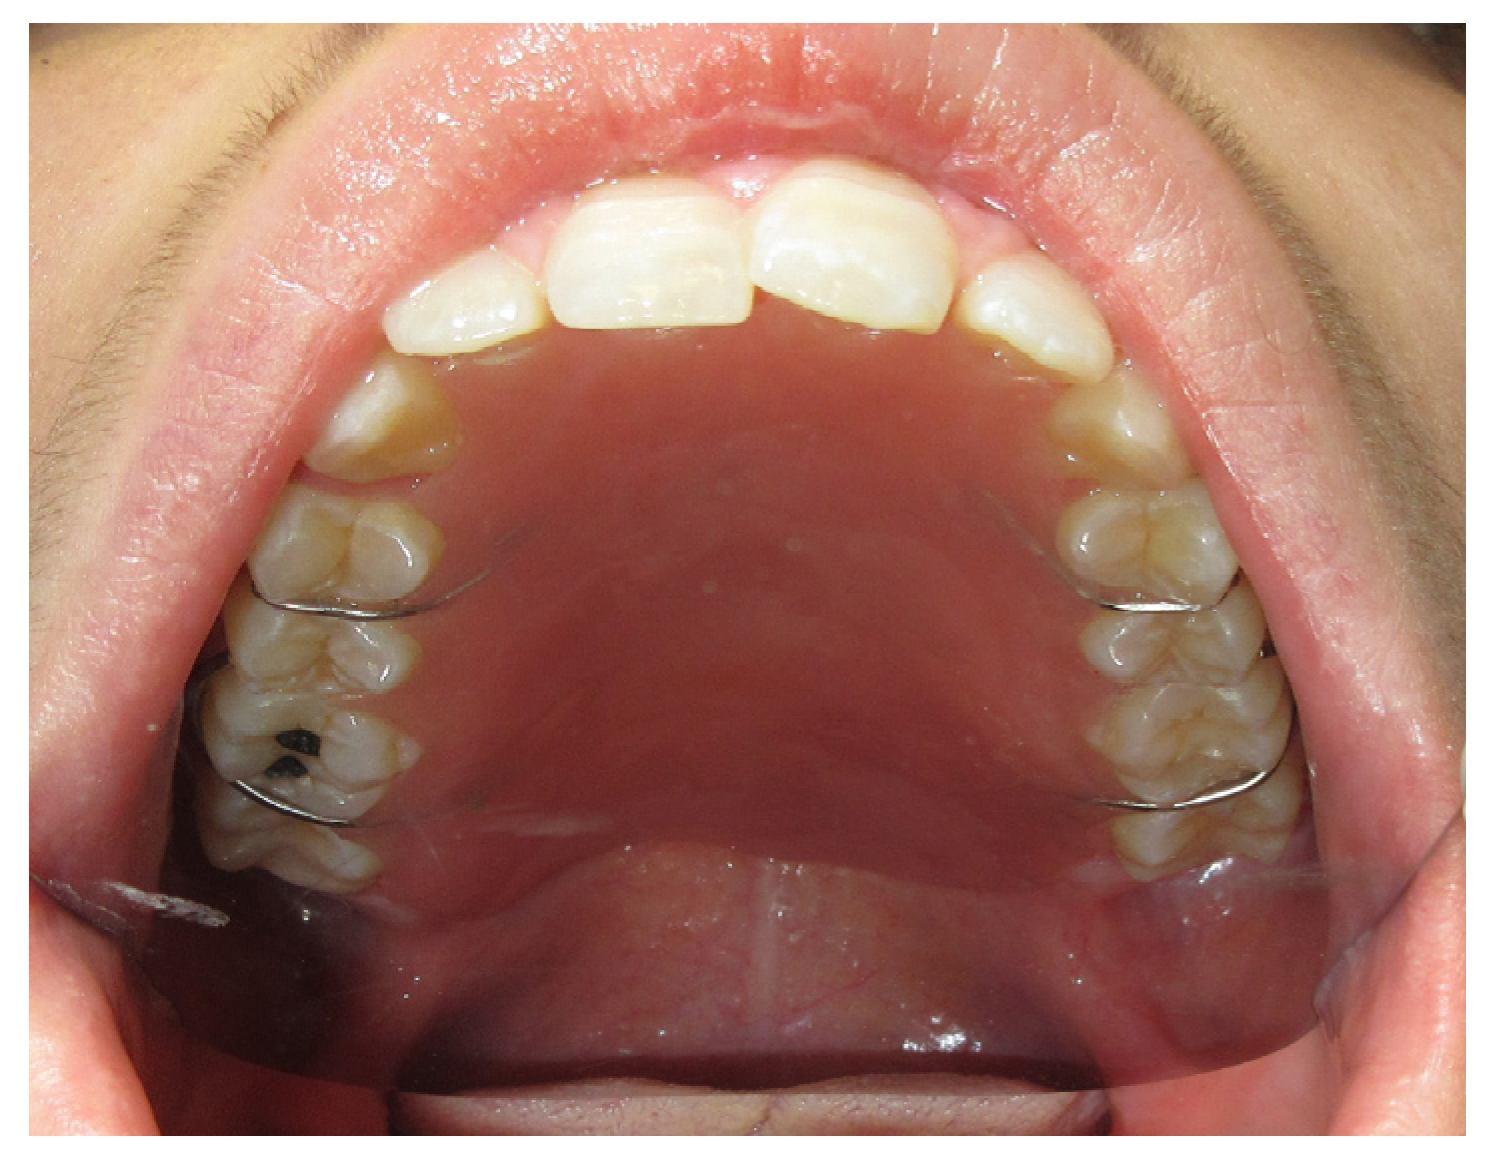

3.1.4. Case 4: P.M.A.

| P.M.A | X | * | 5 | 5 |